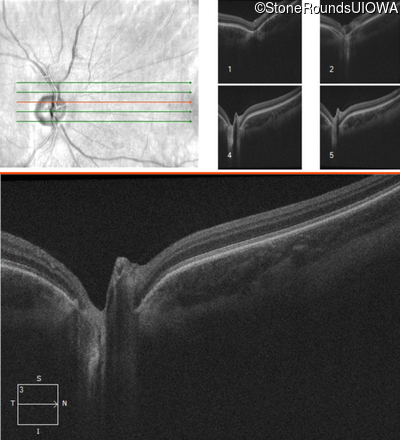

Age at visit: 17 years (Visit 2)

This 17 year old male had normal vision until about 6 months earlier when he began to lose central vision. The left eye may have been affected prior to the right eye.

Diagnosis & molecular findings

Leber Hereditary Optic Neuropathy MT-ND4 11778 A>G   MT